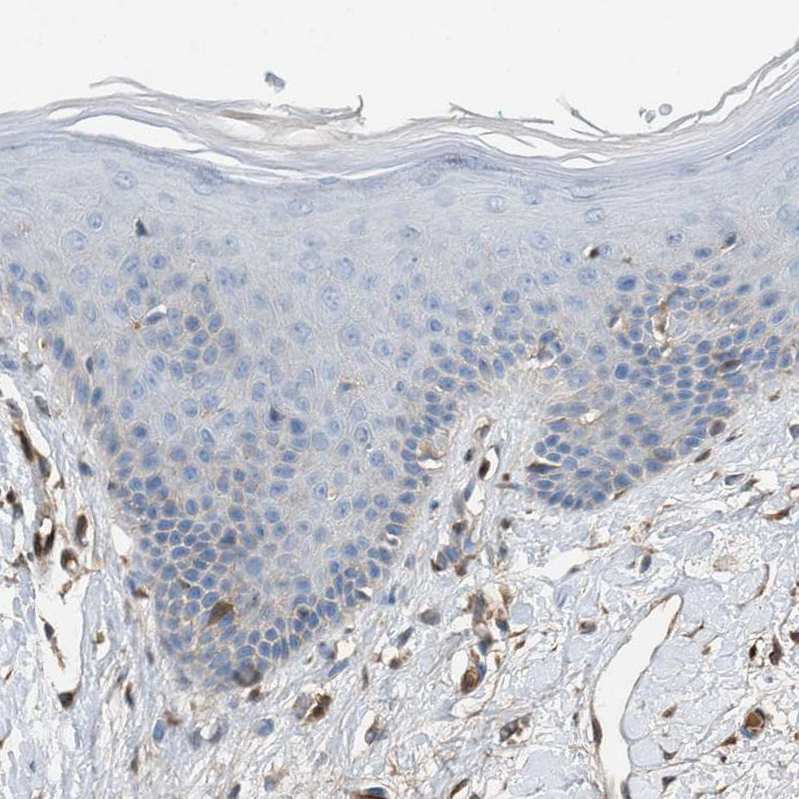

Immunohistochemical staining of human tonsil shows strong cytoplasmic positivity in non-germinal center cells.